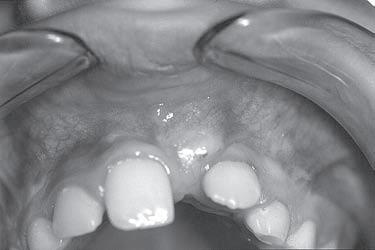

Jsem stále více přesvědčena o tom, že informaci o přítomnosti ortodontické anomálie, která se plně projeví až za několik let, máme k dispozici velmi brzy. Určitá podezření můžeme vyslovit obvykle už při zahájení první fáze výměny chrupu. Jen je třeba dobře se dívat a věnovat pozornost nenápadným symptomům, které na ni upozorňují. Jinak se budeme neustále setkávat s udivenými dospělými pacienty s retinovanými špičáky, s perzistujícími dočasnými zuby a s pacienty, jejichž chrup nelze kvůli ortodontické anomálii dobře ošetřovat.